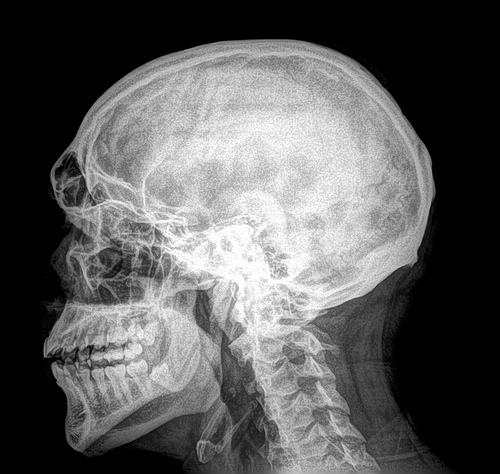

Để điều trị đau răng, nha sĩ sẽ hỏi thăm tiền sử bệnh án cả bạn, sau đó tiến hành thực hiện một số xét nghiệm và kiểm tra. Nha sĩ sẽ hỏi bạn về tình trạng đau răng: thời gian bắt đầu xuất hiện các cơn đau răng, mức độ cơn đau, vị trí tập trung của cơn đau, những điều làm cho cơn đau trở nên nghiêm trọng và những điều làm thuyên giảm cơn đau... Nha sĩ sẽ kiểm tra răng, miệng, nướu, hàm, lưỡi, cổ họng, xoang, tai, mũi và cổ. Sau đó, nha sĩ có thể chỉ định bạn thực hiện xét nghiệm chụp x-quang đầu cổ hoặc các xét nghiệm khác dựa trên nghi ngờ ban đầu về tình trạng đau răng của bạn.